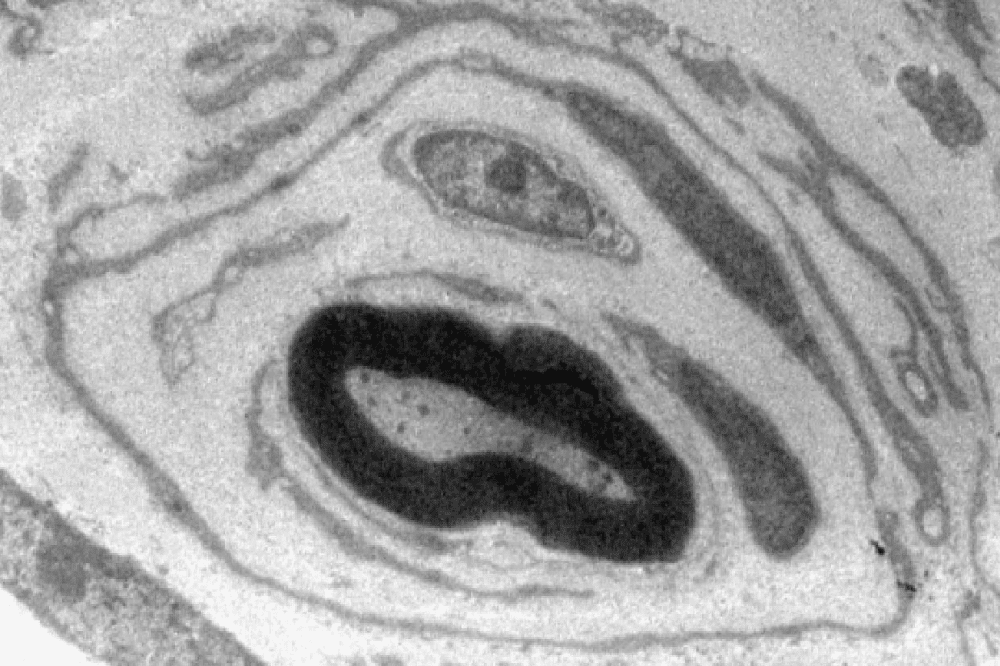

Bei Menschen, die an der häufigsten vererblichen Neuropathie, der CMT1A Erkrankung, leiden, ist die Interaktion zwischen Nervenfasern und Schwann-Zellen gestört. Nerven betroffener Patienten weisen im Querschnitt viele Fasern mit zahlreichen fehlerhaft angelagerten Schwann-Zellen auf. Dieses als „Zwiebelschalenformation“ bezeichnete Phänomen ist schon seit über 100 Jahren bekannt und dient Ärzten seither als wichtiges Diagnosekriterium. Ihre Entstehung ist aber komplett unverstanden.

„In der CMT1A Erkrankung kommt es hingegen zu einer dauerhaften Produktion des Neuregulin-1 Signals in erkrankten Schwann-Zellen. Dies führt dazu, dass die Schwann-Zellen zahlreiche Reparaturbänder bilden, die jedoch in dieser Menge überhaupt nicht benötigt werden. So entstehen schlussendlich die zahlreichen Zwiebelschalenformationen, die wir in Nervenbiopsien von Patienten nachweisen können“, so die Wissenschaftlerin weiter.